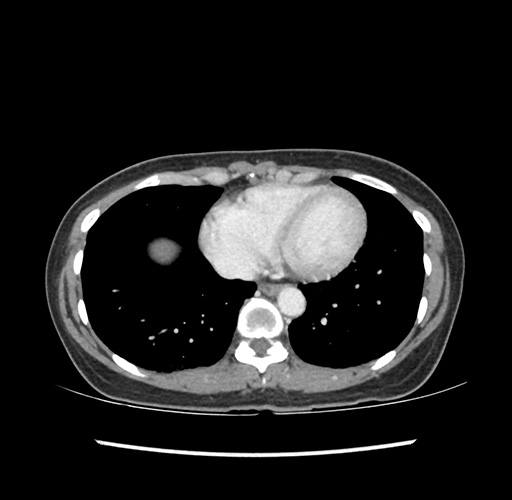

Imaging Analysis

Look through the patient's CT scan to identify any areas of concern for the necessary procedure.

Based on your CT findings, which issue(s) would give reason for "planned slowing down moment(s)" in this case?

Considering a standard left lateral sectionectomy procedure, what step(s) of the operation would you do differently in this case ?